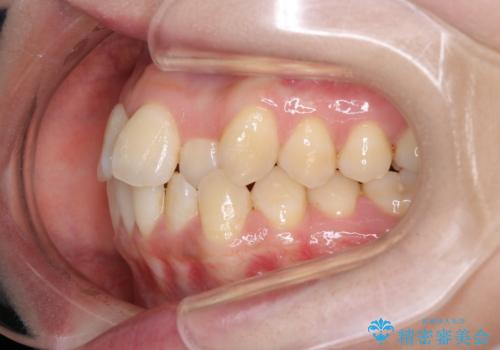

- 前歯のがたつきを治したいという主訴で来院されました。1年後に転勤の可能性があり短期間での治療を希望されました。今回は非抜歯の治療を計画し、IPRと拡大をし、前歯の叢生を改善しました。

前歯のがたつきを治しながら2番の反対咬合も改善させました。短期間で終了し満足していただけました。